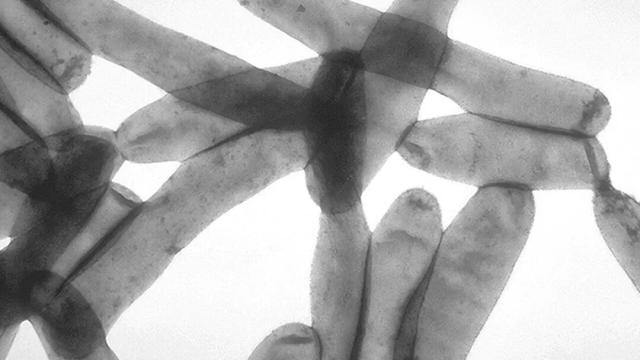

当他将样本放到显微镜下时,眼前的景象让他十分惊讶,样本中存在大量发出“明亮的苹果绿色荧光”的杆状细菌

酒店幽灵,一场宴会与34人的死亡

被分离出来的神秘细菌

难道真的是这种神秘细菌导致了这场疫情肆虐?

为了尽快确定这种细菌与疫情的联系,老麦的实验室迅速对死者的血液样本进行检测,发现其中确实存在着大量抗体。

进一步测试也证实那些因病死亡的患者体内确实存在这些细菌。

这种短杆状细菌,就是本次疫情的罪魁祸首。

引起军团病的病原体是一种短杆状细菌